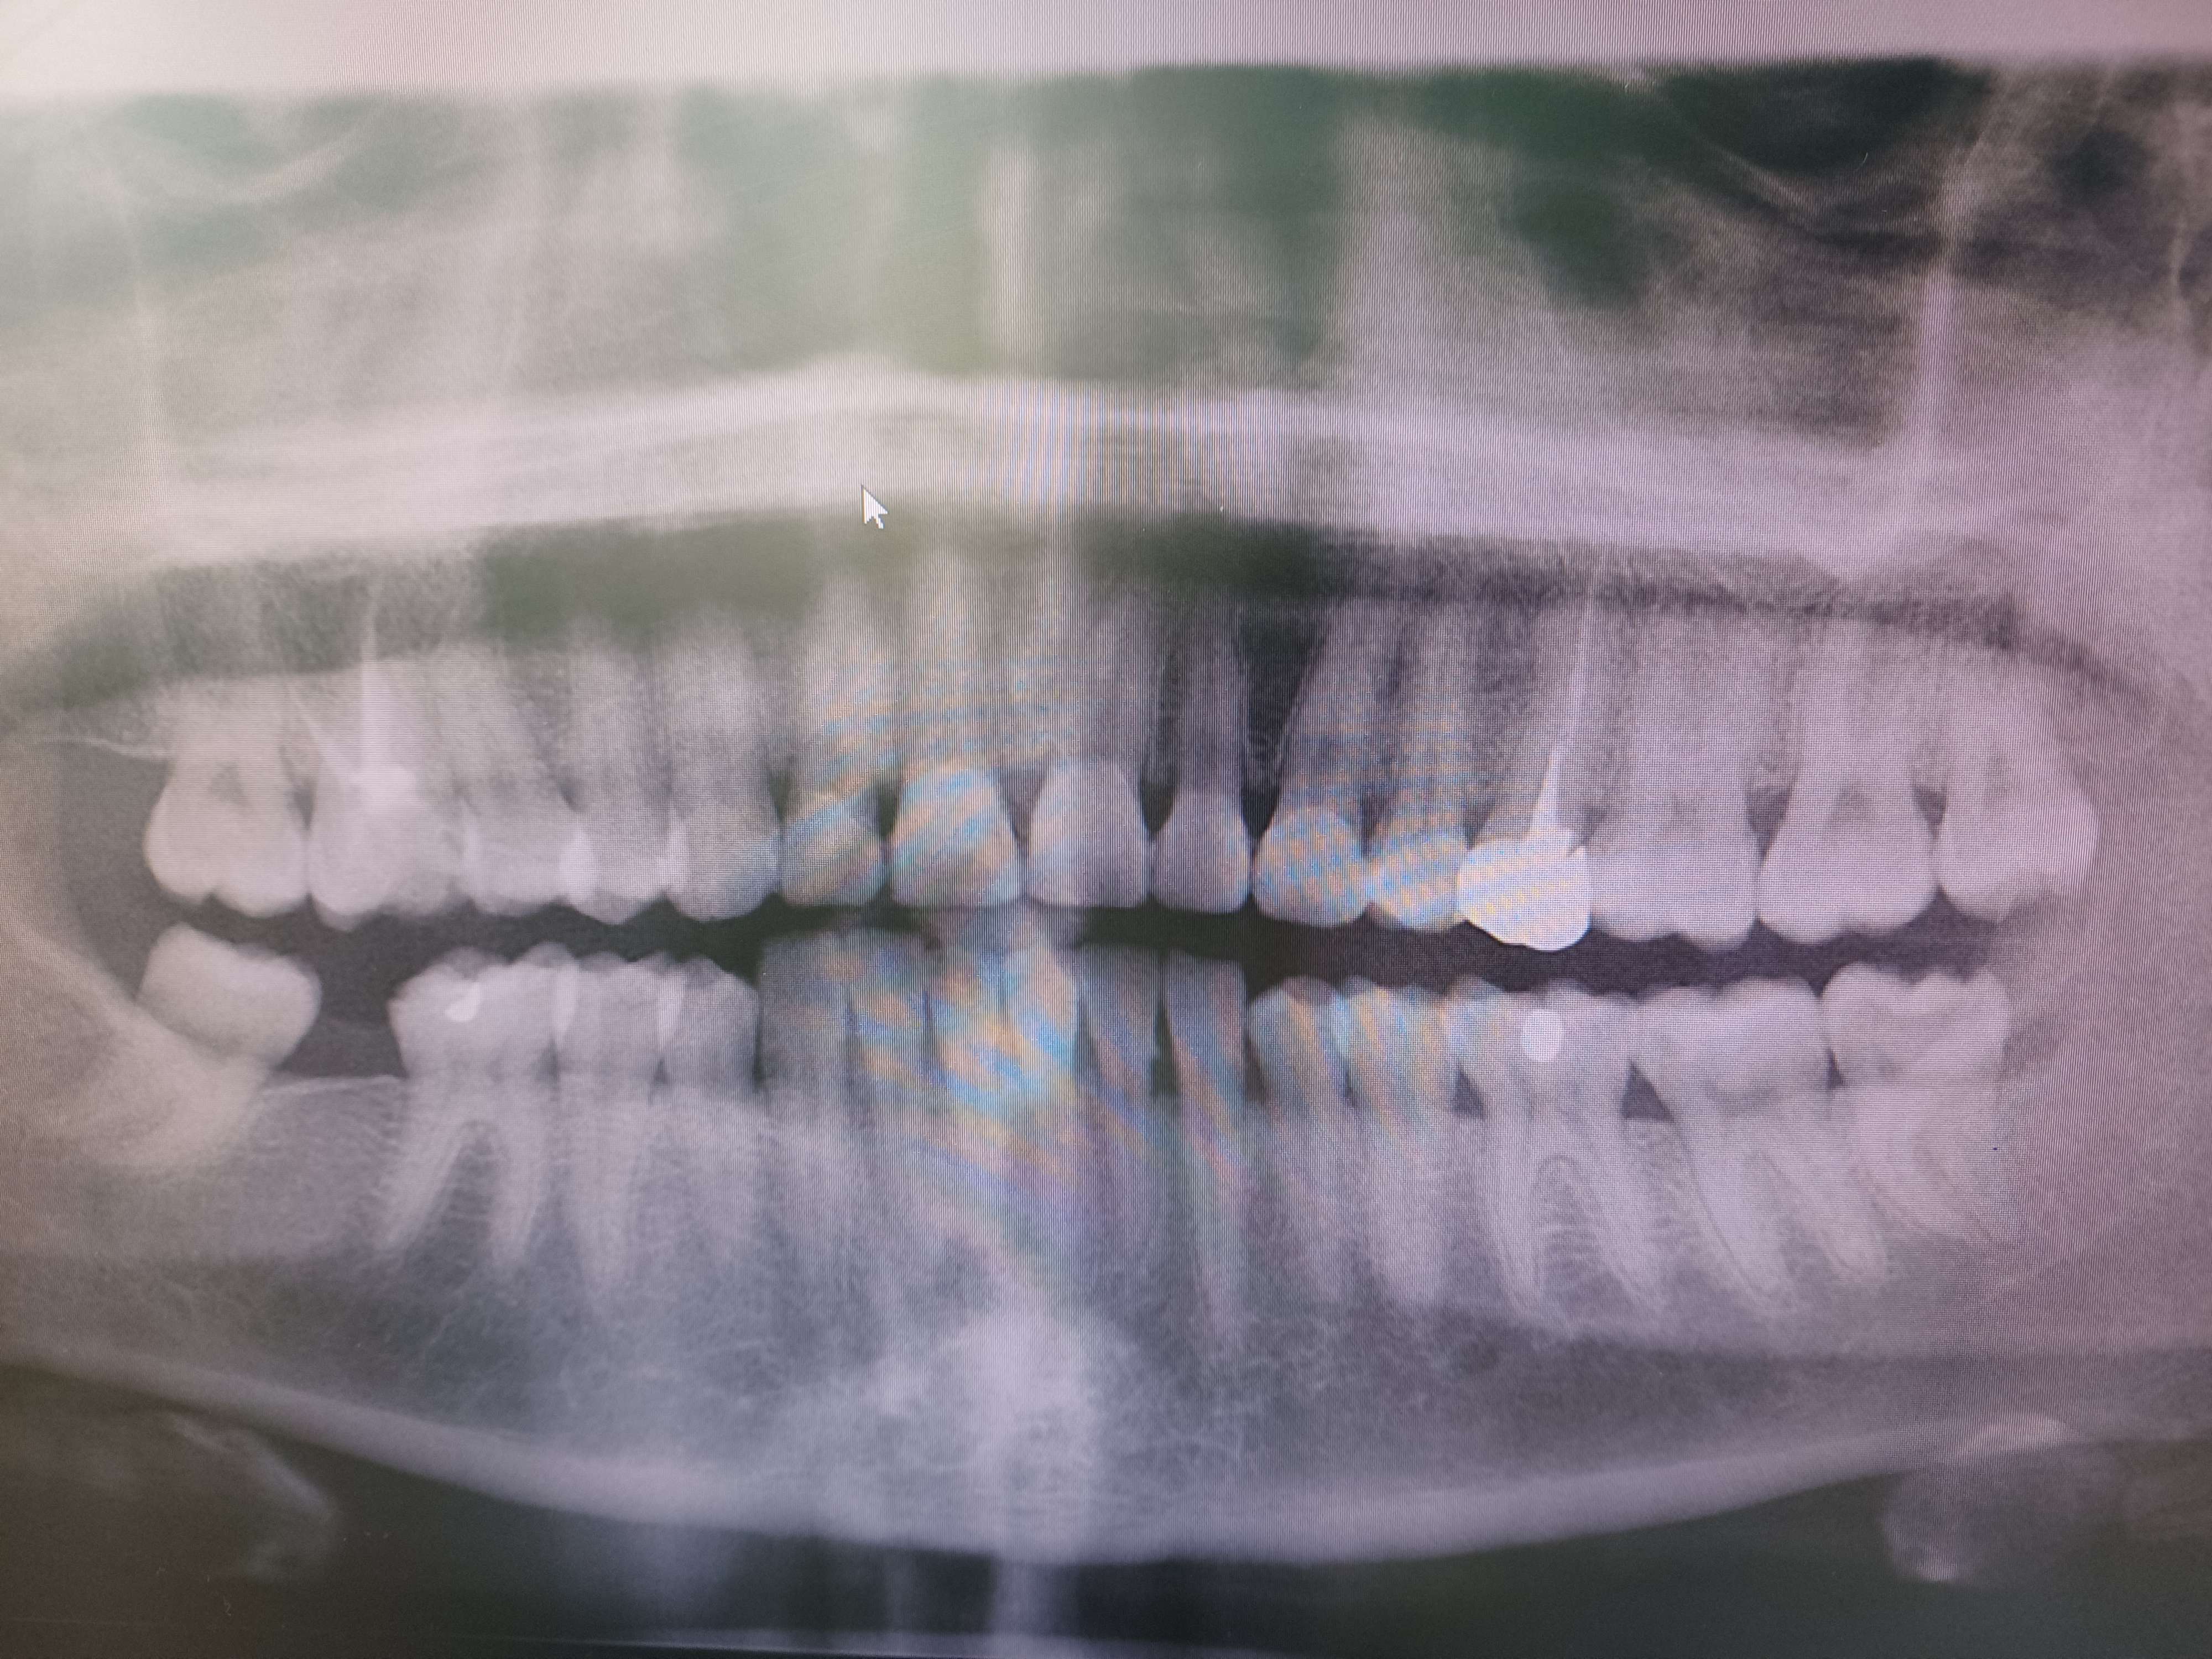

Je vais me faire l'avocat du diable mais au vu de l'état général de ses dents et de son parodonte sur la pano, son hygiène buccale ne semble pas si pourrie.

Par contre que les compos aient été réalisés à la 6 4 2 , cela ne fait guère de doute.

Comment sont les dents postérieures, l’email est sain en l’absence de carie ? On dirait une anomalie de structure sur les dents du bas.

> On dirait une anomalie de structure sur les dents du bas.

Suis du même avis. Les compos ont très probablement été réalisés pour masquer une hypoplasie de l’émail.

Oui enfin, y'a pas un espace interdentaire sans inflammation, en haut comme en bas, même là ou les compos ne sont pas juxta sulcus. Toutes les papilles sont inflammatoires. Donc c'est sûr que faire des facettes, en plus à l'arrache sur ce genre de cas ça ne peut pas donner un joli résultat.

Avant de toucher à quoi que ce soit, il faut régler le problème paro. Là où je te rejoints c'est que sur la pano elle a un parodonte profond correct, donc avec un minimum d'hygiène ça devrait rentrer dans l'ordre. Première étape : brossettes !

Gabzou, Olieve, vous rigolez ou quoi ? à la mandibule où il n'y a pas de facettes compo toutes les papilles sont œdématiées, et encore plus qu'au maxillaire ! une bonne gingivite du bloc inf. Donc OK pour le iatrogène en plus, mais y'a un problème d'hygiène à la base.

Par contre il y a du tartre sous gingival visible à la radio.

Donc pour moi, c'est probablement plus un problème d'hygiène ancien qui a été réglé depuis mais sans détartrage de fait et avec des compos iatrogènes au Mx.